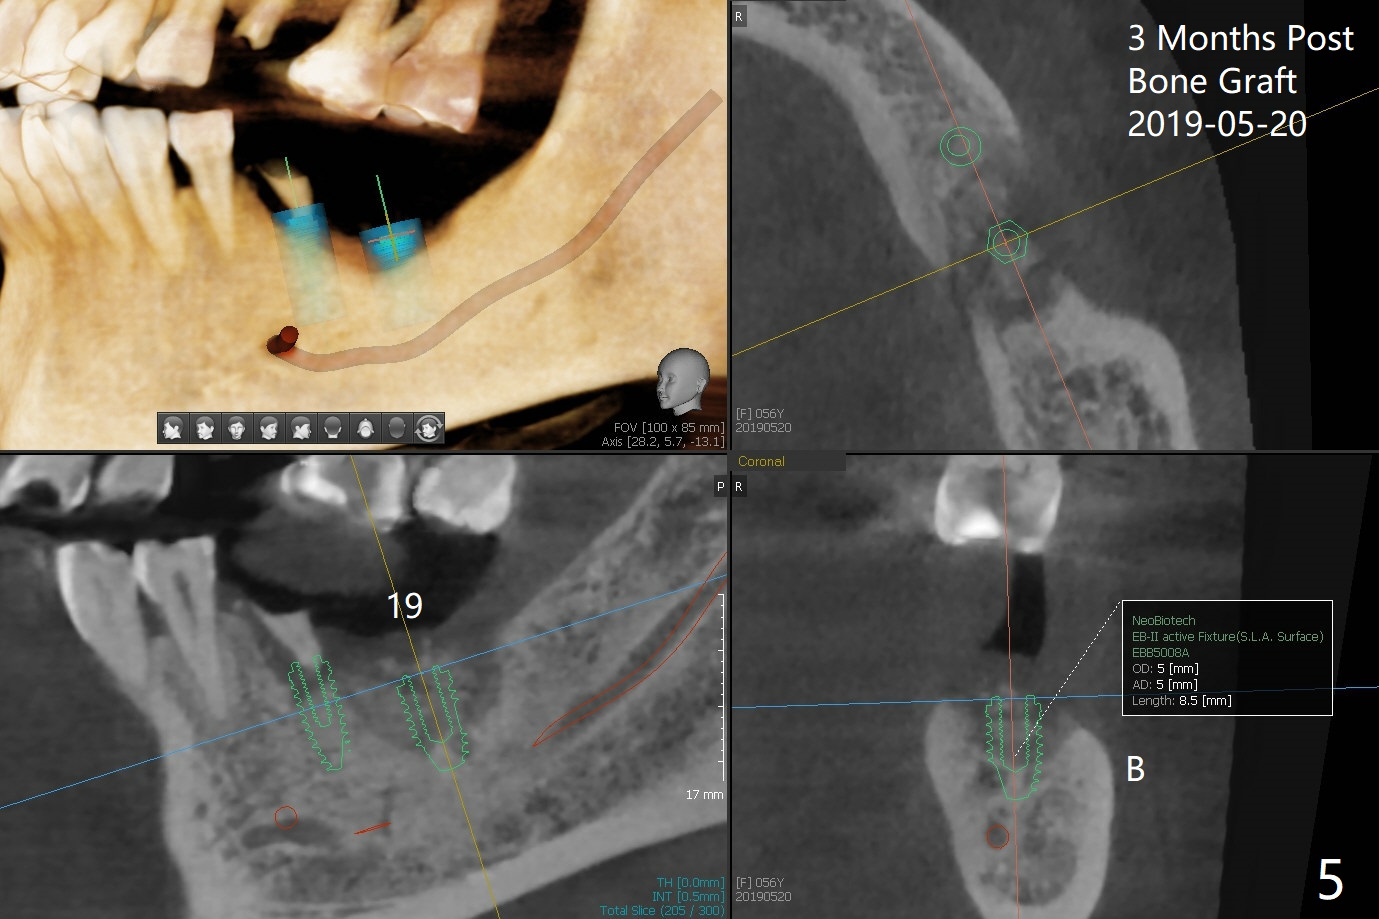

PA is taken after a 2.2 mm drill reaches the depth at #12, since osteotomy is initiated in the mesial slope of the socket (Fig.1 red dashed line) and the neighboring root (*) slightly curves distal. A 8.6x5 mm healing abutment is used to close the socket with the large mesiodistal space after bone graft (Fig.2 *). In contrast, the socket at #20 is large; a 4.5x4.5(3) mm cementation abutment is placed for an immediate provisional to keep autogenous bone (harvested from the site of #18) in place (Fig.3). Six months postop, the patient does not want implant FPD. She wants an additional implant at #19. Since the space between the implants #18 and 20 is 9.41 mm, a narrow implant is indicated (3 or 3.5 mm, Fig.4), in spite of the sufficient buccolingual width (Fig.5). The position and trajectory of the 1.2 mm initial drill and 3x10(2) mm 1-piece implant are acceptable with free hand (Fig.6,7). After 3-4 more turns, panoramic X-ray (Fig.8) and CT (Fig.9) are taken for 28-30 guide. It appears that the 1-piece implant is placed acceptable buccolingual (Fig.9 B). The implants at #12,18,20 (4.5 months postop with guide) are shown in Fig.10-12. It appears that guided surgery is superior in buccolingual position and trajectory to free hand. There is crestal remodeling without implant thread exposure 11 months postop (Fig.13).